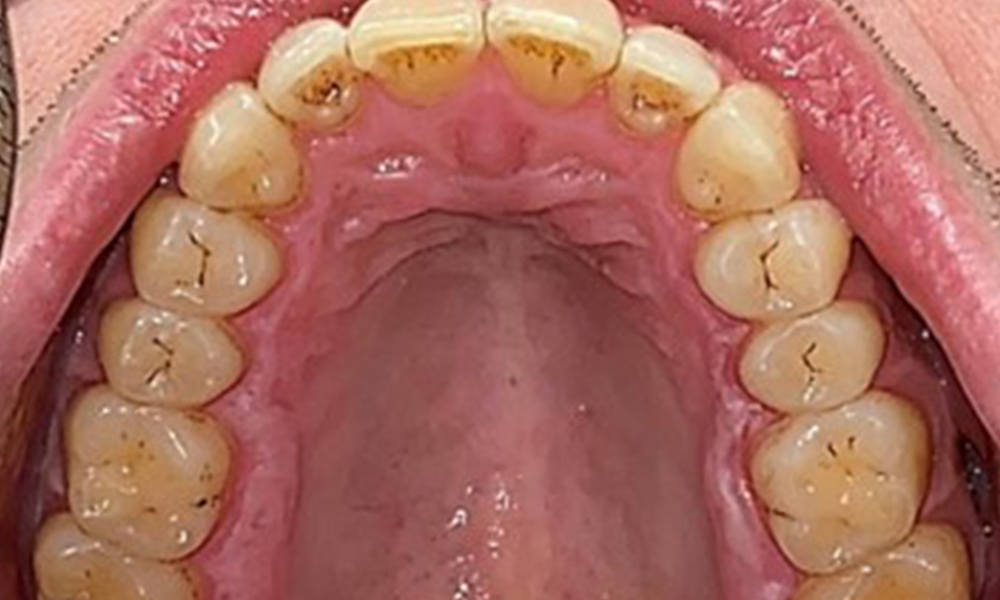

Occlusal view of the maxilla.

Fig. 3: Occlusal view of the maxilla, © Dr R. Krapf

The patient has full dentition with a total of 28 teeth. There were noteworthy erosions and attritions. (Fig. 4, Fig. 5). Due to bruxism, the patient has been wearing a splint with an adjusted bite block at night for many years. The erosions were caused by long-term consumption of isotonic beverages. No periodontal bone loss or active caries were observed.

Full complement of adult teeth with no caries or radiologically recognizable bone loss was observed (Fig. 6). Radiological enamel and cusp loss were particularly evident on 36 and 37.